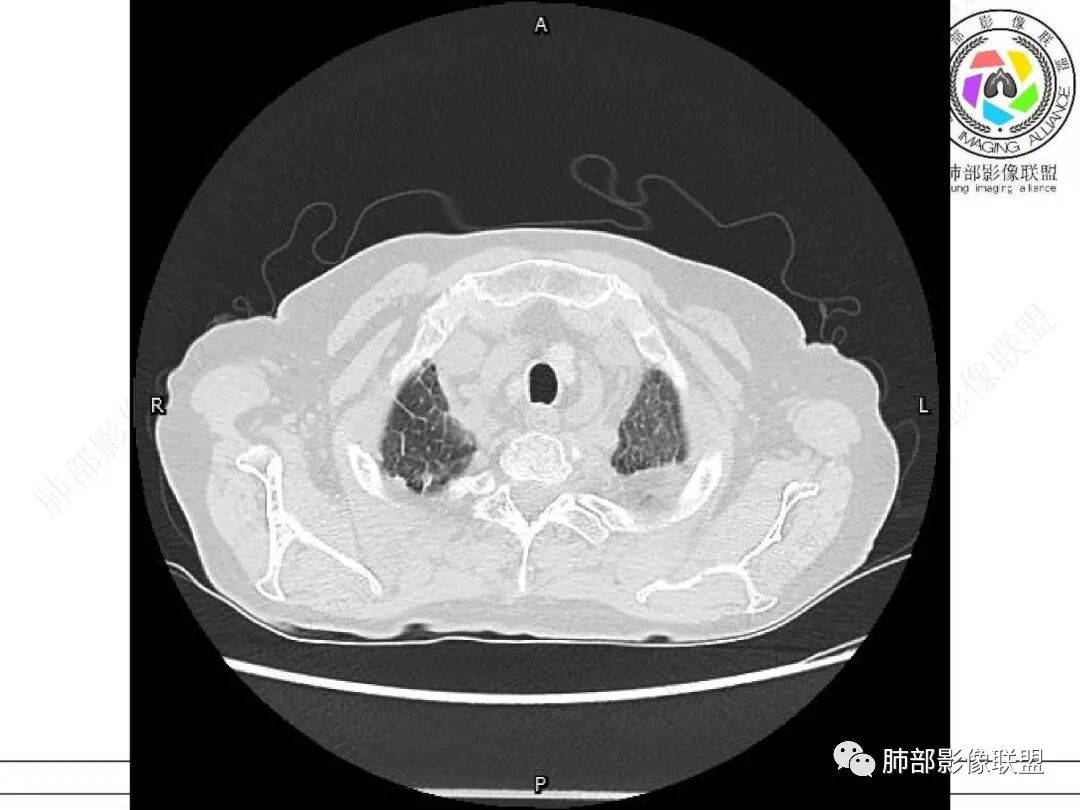

女,71,外阴疼痛2周,发热1周。类风关、高血压、高血糖、卵巢囊肿、肠粘连、胆囊结石等病史及相关药物治疗史。胸部CT:两肺弥漫磨玻璃,血管束增粗,两下肺后肋膈角多发蜂窝,对称分布,双侧胸腔少量积液,纵隔窗心脏大血管影明显增宽。考虑混合性病变,CTD-ILD,并肺水肿?并PJP?。

①影像表现复杂:较弥漫间质性改变,对称磨玻璃密度为主,小叶间隔增厚,有一定重力分布趋势,未见明显纤维化,气囊及蜂窝位于肺边缘,未见典型“月弓征”。心脏影增大,双侧胸腔积液。

②临床方面:老年女性患者,发热(38.5°)、外阴疼痛入院。查体外阴溃疡。

基础疾病较多。长期类风湿性关节炎治疗史。糖尿病病史等。

实验室白细胞不高,C反应蛋白、PCT增高,淋巴细胞显著低(CD4项阙如),G试验值相当高。肾小球滤过率降低,呼衰等等。